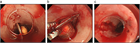

1. 消化管内異物は内視鏡的に摘出可能な場合が多いが、偶発症の可能性も念頭に置き、予め様々な事態を想定、準備、シミュレーションを行ってから内視鏡的摘出に臨むことが推奨される。